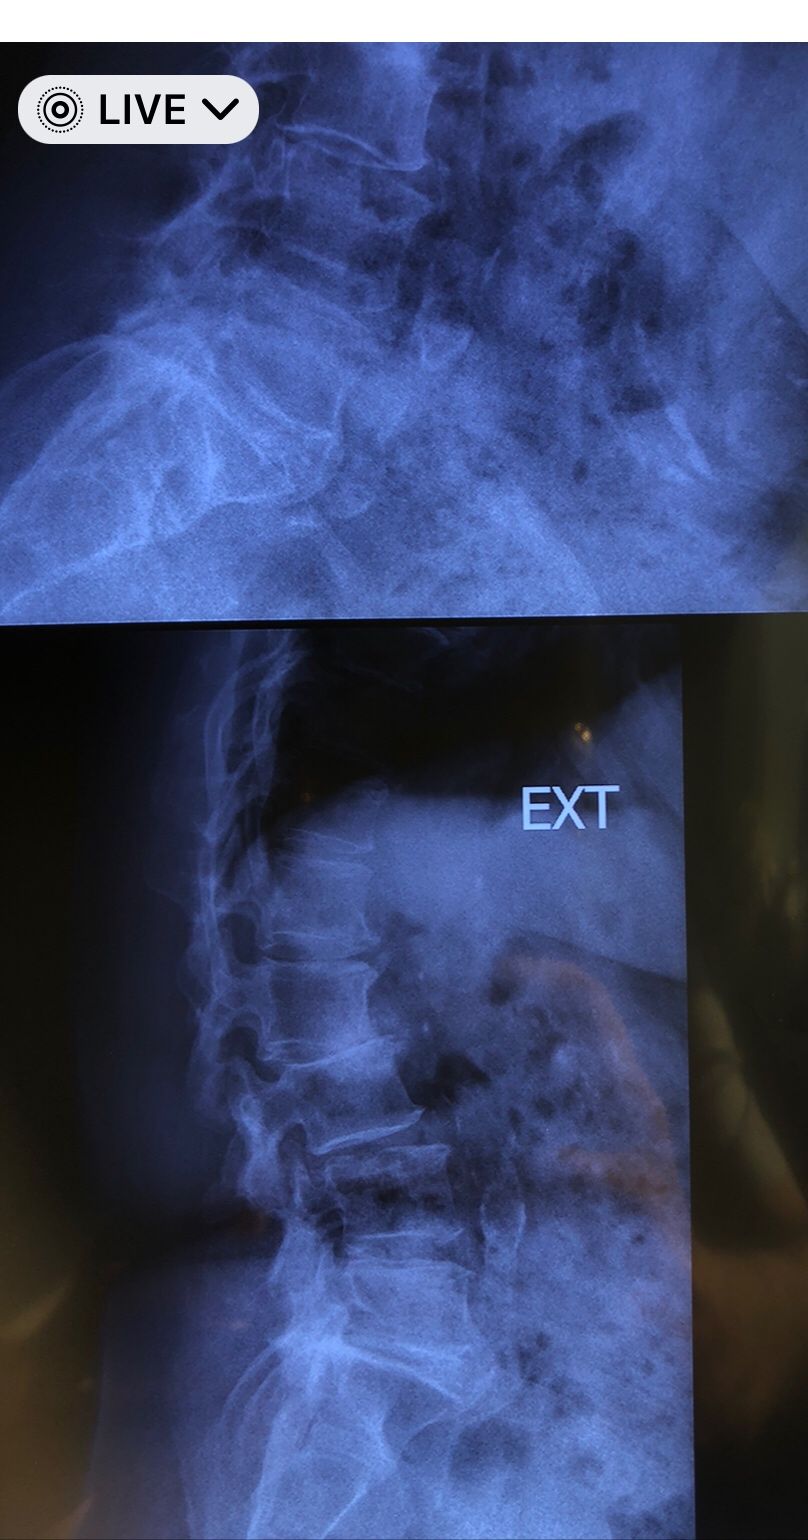

This time presented to my cl with LBP mainly during sleep at night. Just brought me her mri. According to her mri I ordered dynamic L/S X. R.

I didn’t accept her to give treatment. I referred her to her surgeon. What are your findings in her mri and X. Rays?

Is ant listhesis of L4 unstable or stable?

From several compression fractures we see which of is acute/ subacute and which ones are chronic fx?